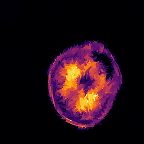

Multi-modality (or multi-channel) imaging is becoming increasingly important and more widely available, e.g. hyperspectral imaging in remote sensing, spectral CT in material sciences as well as multi-contrast MRI and PET-MR in medicine. Research in the last decades resulted in a plethora of mathematical methods to combine data from several modalities. State-of-the-art methods, often formulated as variational regularization, have shown to significantly improve image reconstruction both quantitatively and qualitatively. Almost all of these models rely on the assumption that the modalities are perfectly registered, which is not the case in most real world applications. We propose a variational framework which jointly performs reconstruction and registration, thereby overcoming this hurdle. Numerical results on simulated and real data show the potential of the proposed strategy for various applications in multi-contrast MRI, PET-MR, and hyperspectral imaging: typical misalignments between modalities such as rotations, translations, zooms can be effectively corrected during the reconstruction process. Therefore the proposed framework allows the robust exploitation of shared information across multiple modalities under real conditions.